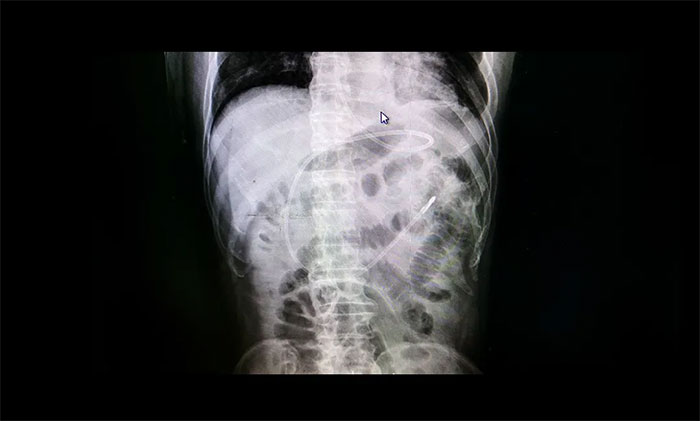

7B病區(qū)醫(yī)護(hù)團(tuán)隊(duì)多次討論治療方案,結(jié)合其病情,最后決定給王先生行“床旁鼻空腸管置入術(shù)”。經(jīng)管床醫(yī)生與患者家屬溝通交流后,患者家屬同意該治療方案。近日,李楠楠護(hù)士長(zhǎng)帶領(lǐng)護(hù)理團(tuán)隊(duì)成功為患者在床旁行鼻空腸管置入術(shù),再經(jīng)過(guò)DR驗(yàn)證,一個(gè)完美的“C”確證空腸管已經(jīng)到達(dá)指定部位!患者開(kāi)始安全“進(jìn)食”。經(jīng)留置鼻腸管后,患者未出現(xiàn)嘔吐、返流等情況,肺部感染及營(yíng)養(yǎng)狀況明顯好轉(zhuǎn)。

▲DR驗(yàn)證,空腸管已經(jīng)到達(dá)指定部位